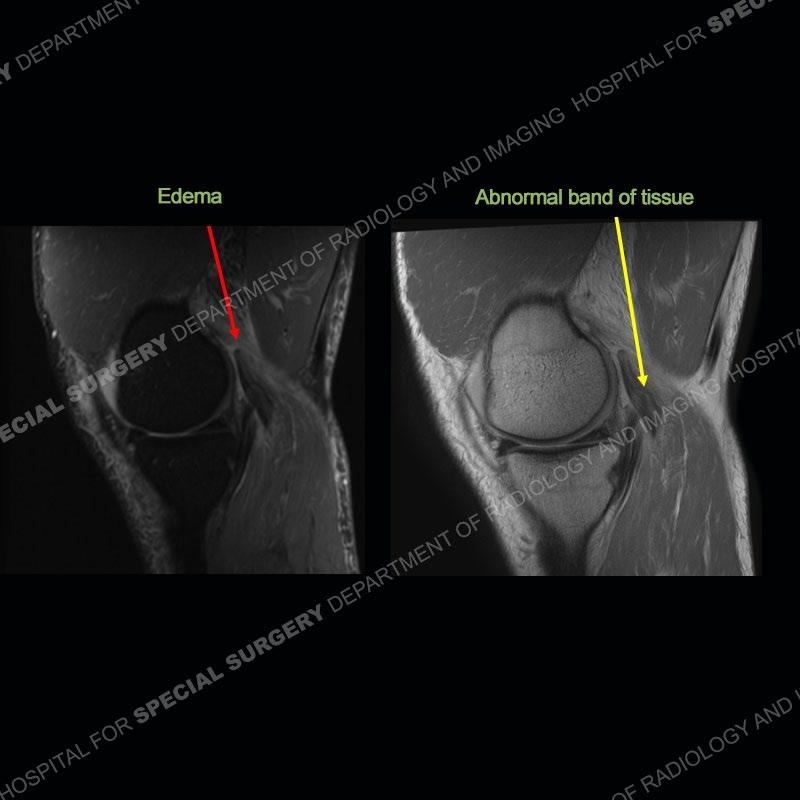

The radiographs show degenerative change of the medial compartment and a varus knee, but they are not germane to this case. No acute bony injury is present. The MRI shows edema of the posterior medial knee/soft tissue and a focal area of a partially disrupted low signal structure. The details are kept at a minimum in the findings of this case on purpose.

The findings were kept purposefully vague as identifying the structures early on takes away a lot of the diagnosis. An uncommon entity and one of which we do not see a lot. Enthesopathic changes and tendinosis are seen as are distal MHG injuries, but proximal tears are rarely present. This case highlights a number of points. One, it almost always comes down to anatomy. Perhaps not a structure we normally spend too much time on, except save for diagnosing a Baker’s cyst, but knowing where this structure and all structures exist in all three planes is imperative. Second, when you think you are making a “call” or finding that you have never made before, step back and think is this just the abnormal presentation of a common pathology. That situation arises much more frequently. Third, if you look at it once, twice, and probably a third time and are confident in your odd or very rare diagnosis, stick to your guns. Especially, when it comes down to anatomic structures, the proof will be in the images.

Fourth, use all imaging planes and different pulse sequences to make your diagnosis. The edema highlighted in this case can be seen as the obscuration of fat on the PD images but is much easier to perceive as the high signal on the IR pulse sequences. The actual disruption of the MHG myotendinous junction is only able to be seen on the axial images. On the sagittal and coronal images, we get a sense something is wrong but hard to be exact. Lastly, when you look at a study and something just seems off (as I would say the sagittal and coronal images do with that dark band of tissue posteriorly), listen to yourself and go through the study slowly and meticulously. Most of the time you will find you were right, and something indeed is present.